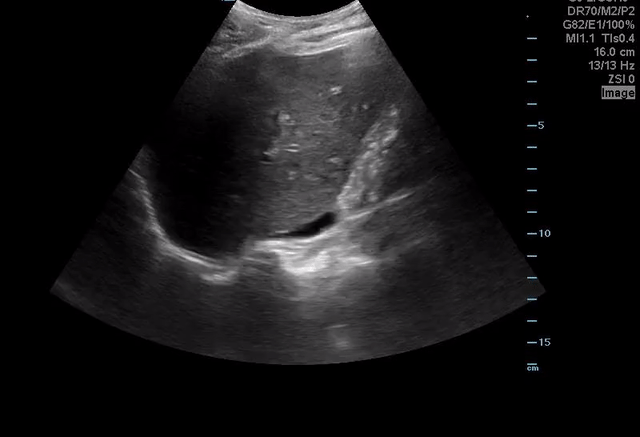

COTW 03/21: A 77-year-old female with urinary retention and flank pain

73-year-old female with a PMH of HTN, Hx. Renal CA, Hx. R-subclavian steal syndrome, Hx. Carotid angioplasty who presents with urinary retention status post mechanical fall 3 days ago. Patient has left sided rib pain, currently on Plavix and aspirin. Patient notice a bruise developing to her back/flank area and has not been able to urinate for the past 16 hours.

Vitals: BP:161/79 | Pulse: 81 | Temp: 95.8 °F| Resp: 18 | SpO2: 99 %